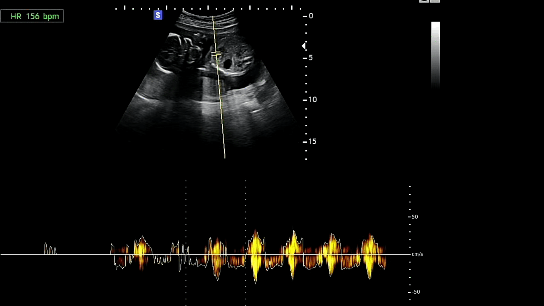

[심장박동수 : 156bpm]

호띵이는 건강하게 잘 크고 있다. 그리고 이번 초음파에서는 호띵이 얼굴을 간접적으로 볼 수 있었다.